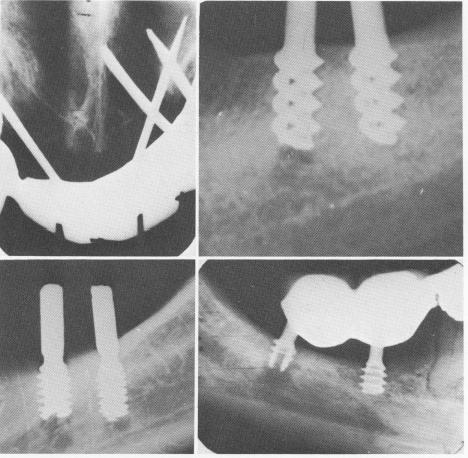

Fig. 14-13. A, Pin implants are deeply embedded in the nasal vestibulum. B, A number of operative mistakes caused failure with the implants. The trephining of bone below the first implant perforated the mandibular canal. Also, the spirals were too close to the alveolar crest. A two- to three-spiraled implant should have been used insted of the four-spiraled one. (Arrow points to area of canal perforation.) C, Both helical burs penetrated the canal, causing temporary paresthesia. However, the most posterior implant was also set into the mandibular canal and had to be removed. D, The posterior implant was not firmly anchored because the underlying bone was overtrephined with the helical bur. In most situations where the canal is involved either by the instrumentation prior to the implant insertion or by the implant itself, a paresthesia is usually the result.

resistance from a spicule of bone and assume that the bottom of the prepared hole has been reached. He thus leaves the implant too high, causing the invagination of epithelial tissue into the spirals.

Setting the implant as deep as the prepared hole is usually a problem only with the spiral-shaft implant, and a number of failures—particularly by a timid, inexperienced operator—may result (Fig. 14-15). The operator should always carefully check his x-rays and review his previous estimates as he seats the implant. When he is sure that the implant has not been set deeply enough and yet he feels resistance, the hole should be widened so that the spiral-post implant can be inserted to its maximum depth. As has been previously mentioned, forcing an implant—particularly a spiral-post implant—into its site may result in the implant's breaking.